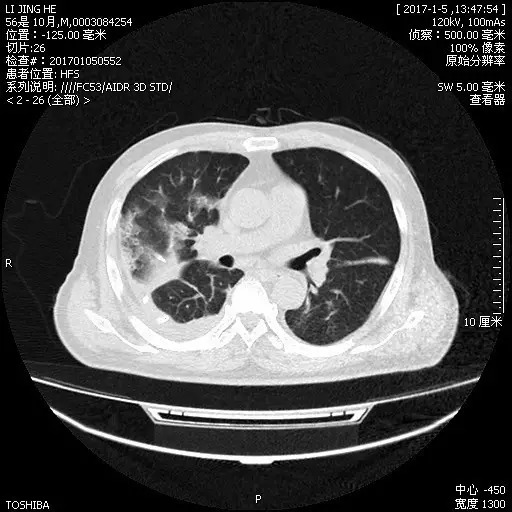

经抗感染治疗后,复查肺CT示肺部病变较前好转(图10)

图10.2017年1月5日胸部CT

于2017-01-10拔除引流管,于2017-01-12抗生素降阶梯为头孢西丁2.0静滴Q8h联合替硝唑0.4静滴Qd,患者病情好转出院。2017-03-10门诊复查胸部CT示肺内渗出及右侧胸腔积液较前进一步吸收(图11)。